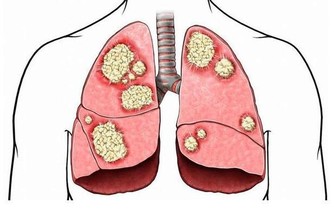

痛風病發生在任何年齡,但最常見的是40歲以上的中年男人,

並且發病人群有越來越年輕化的趨勢,這是為什麼呢?

痛風是一種常見的疾病,現在越來越多的年輕人患上了痛風,下面就為大家介紹一下年輕人易患痛風的原因是什麼,希望對大家有所幫助,減少年輕的痛風患者,對於痛風的治療,一定要引起大家的重視,並且要儘早的進行治療。

根據調查顯示:痛風患者的初發平均年齡在不到20年的時間裡下降了6.3歲,開始襲擊年輕人。據分析發現,痛風的初次發病年齡有明顯年輕化的趨勢,不足40歲的初次發病者增加了26.3%。